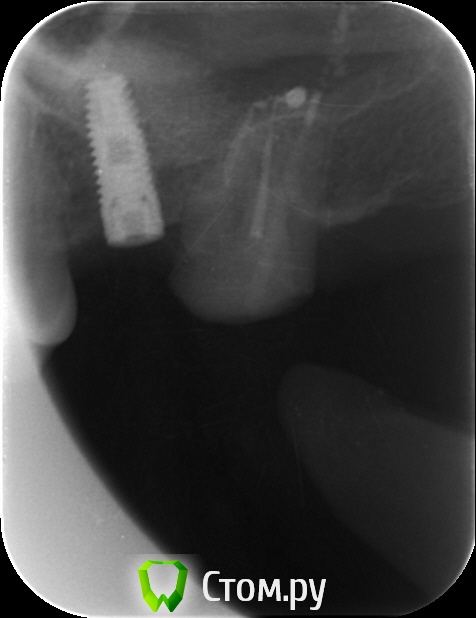

an_ver Опубликовано 29 мая, 2014 Поделиться Опубликовано 29 мая, 2014 Закрытый синус.Набор SCA.SPI 3,75*10 мм 5 Ссылка на комментарий

4ebstom Опубликовано 29 мая, 2014 Поделиться Опубликовано 29 мая, 2014 Имплант недокручен или снимок такой? Ссылка на комментарий

an_ver Опубликовано 29 мая, 2014 Автор Поделиться Опубликовано 29 мая, 2014 Имплант недокручен или снимок такой?Наверно снимок косой)) Счас с формиком ходит.Поставлю коронку отфотаюсь))) Ссылка на комментарий

NickN Опубликовано 29 мая, 2014 Поделиться Опубликовано 29 мая, 2014 Закрытый синус.Набор SCA.SPI 3,75*10 ммНа снимке насадка SCA один в один к МИСовском наборе для компрессии)) Какой графт использовали? Ссылка на комментарий

zzkz Опубликовано 30 мая, 2014 Поделиться Опубликовано 30 мая, 2014 1. Сколько в итоге подняли?2. Имплант какой длины?3. У Вас Rg в кабинете стоит? Ссылка на комментарий

an_ver Опубликовано 30 мая, 2014 Автор Поделиться Опубликовано 30 мая, 2014 1. Сколько в итоге подняли?2. Имплант какой длины?3. У Вас Rg в кабинете стоит?1. 4 мм 2.3,75*10 мм SPI 3.Rg да,в каждом своя пушка...дорого но удобно..RVG без проводов Дигора Ссылка на комментарий